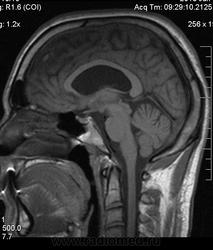

Мужчина 32 лет. Из анамнеза: перинатальное повреждение ЦНС, ДЦП, дизартрия, правосторонний верхний монопарез. С 16 лет приступы эпилепсии.

Аплазия прозрачной перегородки. Шизэнцефалия с открытыми краями в лобно-теменной области слева. Шизэнцефалия с закрытыми краями в лобной области справа? Утолщение коры по контуру расщелин и в области глазничной извилины правой лобной доли. Микрогирия? Гиперостоз костей свода черепа. Уважаемые коллеги, возможно я ошибаюсь, или есть еще аномалия?

На мой взгляд, полимикрогирия двусторонняя (конвекситальные отделы дорзальных отделов лобных долей и частично теменных, а также в базальном отделе полюса правой лобной доли) + закрытая шизенцефалия левой лобно-теменной области. Аплазия прозрачной перегородки (как признаки лобарной голопрозенцефалии).